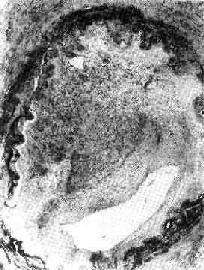

无论心或动脉、静脉内的血栓,其形成过程都从血小板粘附于内膜裸露的胶原开始。当内源性和外源性凝血途径启动后最后产生的凝血酶将纤维蛋白原水解,其纤维蛋白单体再聚合成纤维蛋白多聚体(纤维素)。纤维素和内皮下的纤维连接蛋白共同使粘集的血小板堆牢固地粘附于受损内膜表面,不再离散,形成境下均匀一致、无结构的血小板血栓,电子显微镜下,血小板彼此紧密接触,轮廓仍然保存,但内部颗粒已消失。在血小板与血小板之间有少量纤维素存在(图3-3)。

图3-3 血小板粘附

血管内皮细胞脱落,血小板粘附在暴露的纤维结缔组织上

(电子显微镜照片)(采自Anderson)